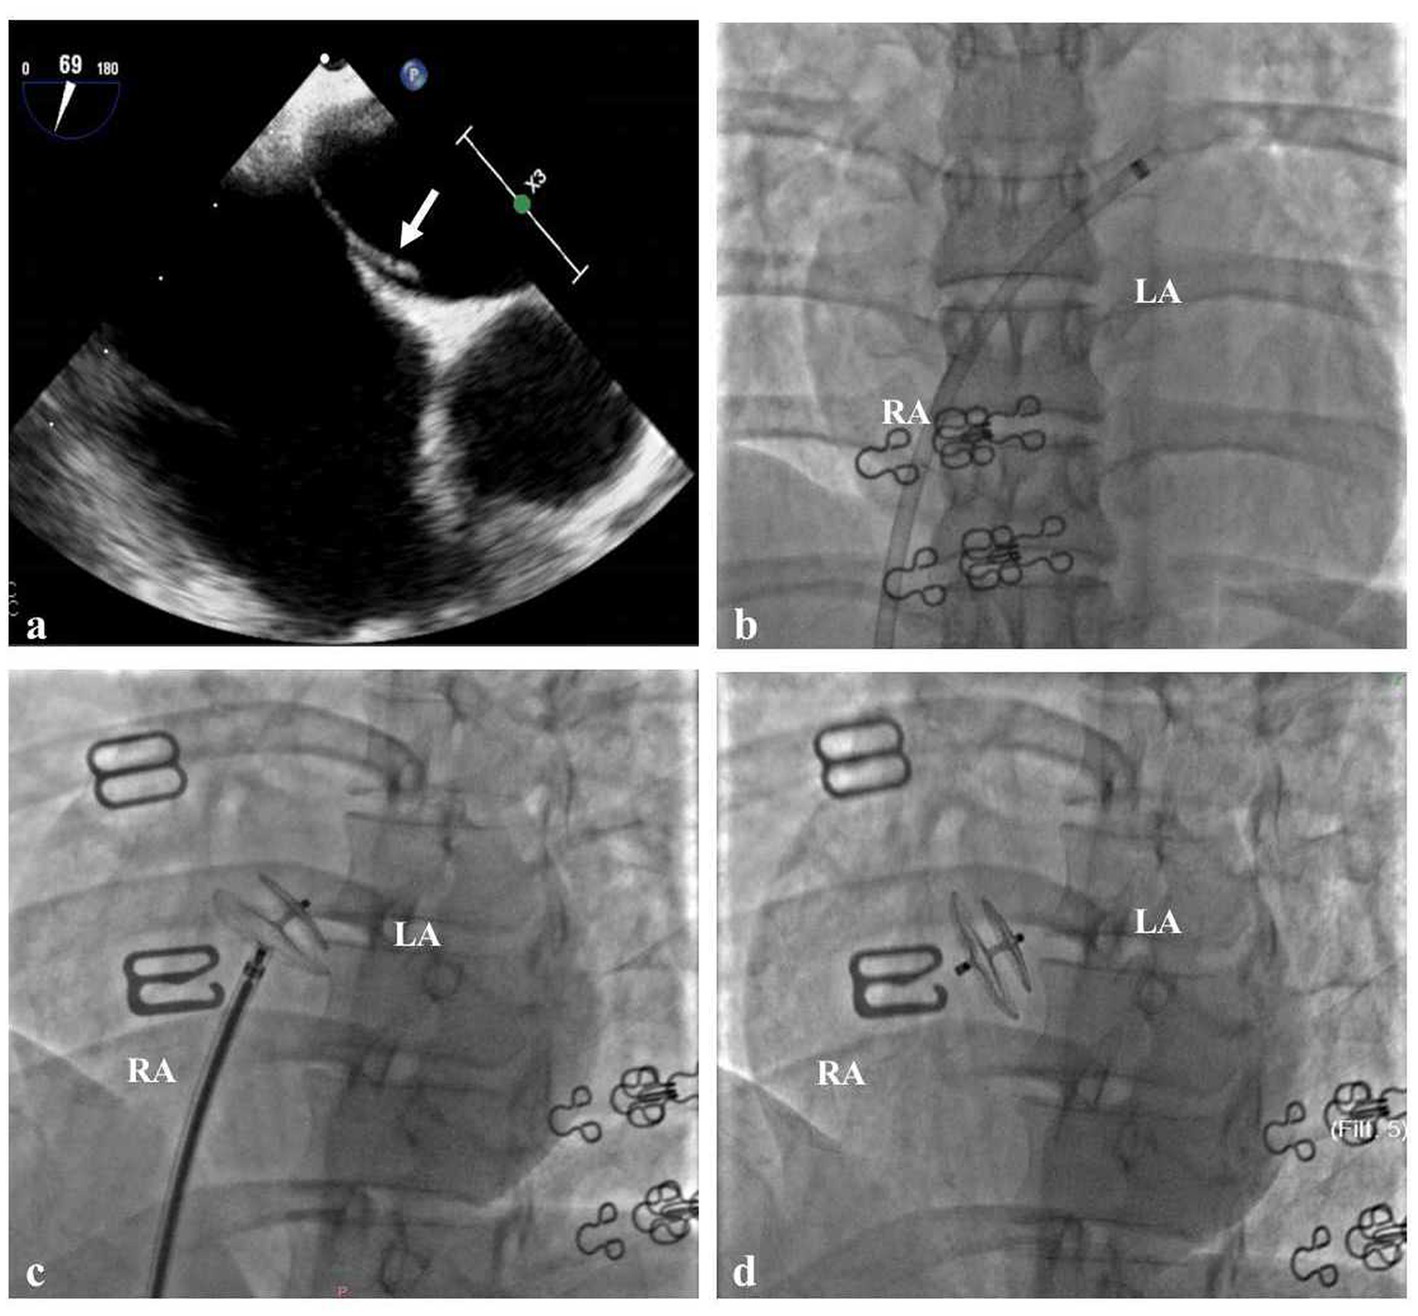

When she was 34 years old, she was readmitted to the hospital because of right-sided limb weakness and a headache. A brain magnetic resonance imaging (MRI) scan during headache attacks with hemiparesis (Figure 1A) revealed no significant abnormalities. Computed tomography angiography revealed left vertebral artery hypoplasia (Figure 1C). During hospitalisation, a PFO with right-to-left shunting was observed. Transoesophageal echocardiography showed that her PFO was “long tunnel”-like (Figure 2A), which carried a higher risk of thromboembolic events. Blood tests, liver and kidney function tests, thyroid function tests, coagulation studies, and immunological examinations revealed no significant abnormalities. After evaluation by the cardiovascular department, she underwent transcatheter PFO closure according to the guidelines (11) and was discharged 2 weeks later (Figures 2B–D).

Figure 2

Cardiac Imaging in the Patient (A) Transoesophageal echocardiography showed that the patent foramen ovale was long tunnel-like (white arrow). (B) The delivery sheath passes through the PFO from the right to the left atrium. (C) The traction test of PFO closure was successful. (D) Made occluder successfully released.